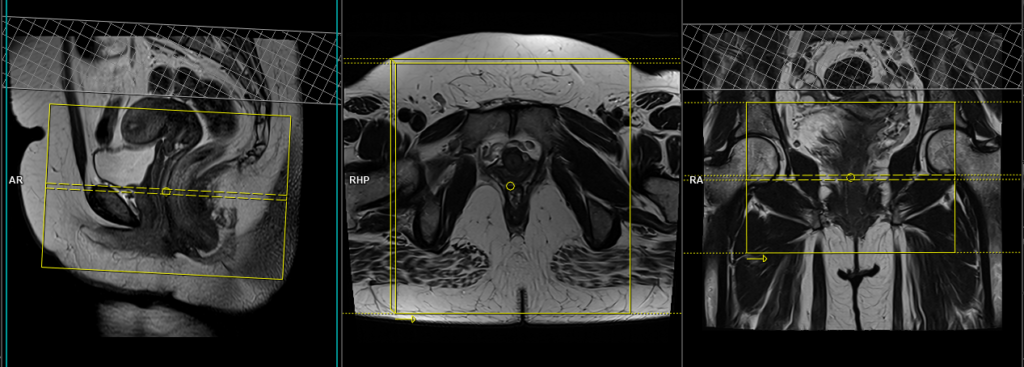

T2 tse fat sat (or stir)axial oblique 3mm small fov

Plan the axial slices on the sagittal plane and angle the planning block perpendicular to the vaginal canal. Check the planning block in the other two planes. An appropriate angle must be given in the coronal plane (perpendicular to the vaginal canal). The slices must be sufficient to cover the entire vaginal canal from 1 cm above the cervix down to 1 cm below the anal opening. The FOV (Field of View) must be small to produce a high-resolution scan of the rectovaginal area (usually 150 to 200).

Parameters

TR 5000-6000 | TE 110 | FLIP 130 | NEX 5 | SLICE 3 MM | MATRIX 256X256 | FOV 150-200 | PHASE R>L | GAP 10% | FAT SAT SPAIR |